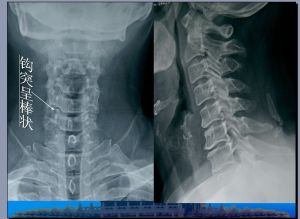

方法:回顧分析40例經彩色都卜勒檢查發現椎動脈供血不足的頸椎病患者鉤椎關節的X線平片影像學改變。

結果:40例頸椎病患者其頸椎鉤突肥大、變尖延長、彎曲以及骨贅形成35例(85%);鉤椎關節變窄,關節面顯示硬化5例(15%),並可伴有頸椎椎體前後緣骨刺形成、韌帶骨化等X線影像學改變。

結論:頸椎X線平片簡便、費用低廉,對鉤椎關節影像學改變的初步觀察.可提示椎動脈型頸椎病的存在,具有一定的臨床價值。